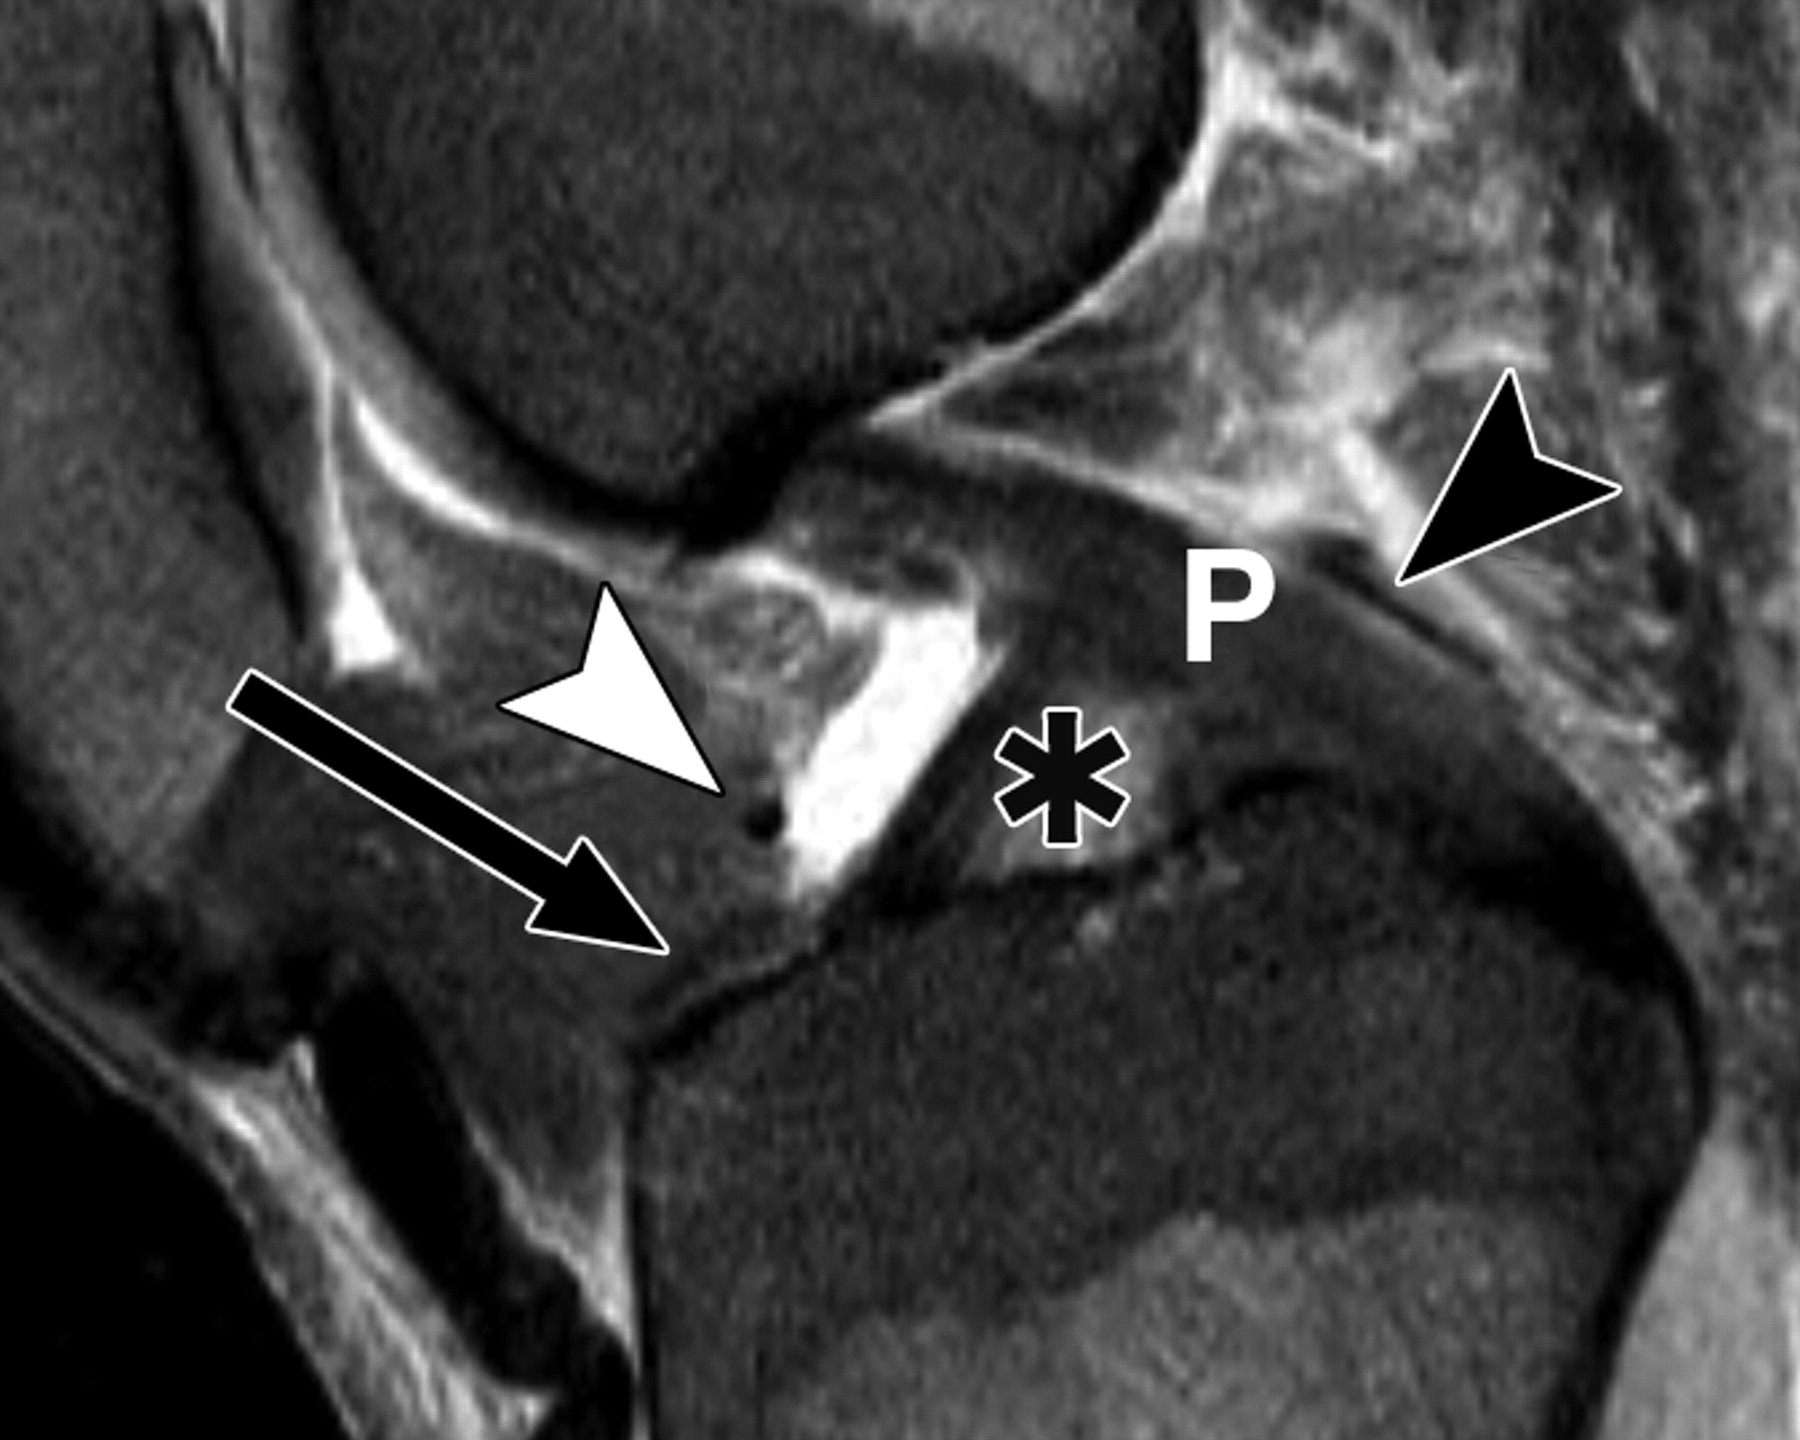

图5A-59岁男性。

中等加权、脂肪饱和、快速自旋回波(TR/TE有效值,3,700/29)3-T MR图像显示半月板后根和交叉韧带的解剖关系。

冠状面MR图像显示内侧半月板(MM)后根(箭头)覆盖后髁间区域的一个以上切片厚度。LM =外侧半月板。LT =胫骨外侧结节。

图5 B-59岁男性。中等加权、脂肪饱和、快速自旋回波(TR/TE有效值,3,700/29)3-T MR图像显示半月板后根和交叉韧带的解剖关系。

冠状面图像依次位于A的腹侧,显示外侧半月板后根(LM)(白色箭头)和内侧半月板后根(MM)(黑色箭头,B)的插入,覆盖后髁间区域的一个以上切片厚度。MT =胫骨内侧结节。

图5C-59岁男性,中等加权、脂肪饱和、快速自旋回波(TR/TE有效值,3,700/29)3-T MR图像显示半月板后根和交叉韧带的解剖关系。

图5D-59岁男性,中等加权、脂肪饱和、涡轮自旋回波(TR/TE eff,3,700/29)3-T MR图像显示半月板后根和交叉韧带的解剖关系。

通过后交叉韧带(P)的矢状图像显示内侧半月板后根的插入部位(箭头)相对于韧带插入部位位于前方。MT =胫骨内侧结节。箭头表示膝前韧带。

图5E-59岁男性,中等加权、脂肪饱和、快速自旋回波(TR/TE,3,700/29)3-T MR图像显示半月板后根和交叉韧带的解剖关系。

通过前交叉韧带(星号)的MRI图像显示外侧半月板后根的附着点(箭头)相对于内侧半月板的附着点稍靠前。圆圈表示前交叉韧带和外侧半月板前根的共同附着点。箭头表示膝前韧带。P =后交叉韧带。